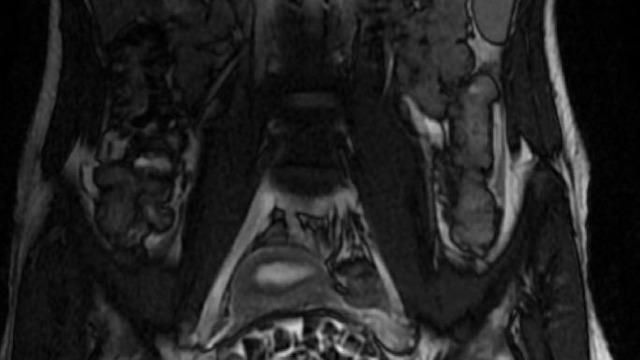

Hastasının durumuna yönelik konuşan Üroloji Uzmanı Doç. Dr. Erkan Erkan, "Hastamızın 2004 yılında doğduğunu ardından doğar doğmaz ekstrofi vezika dediğimiz 50 binde bir görülen bir anomaliden dolayı art arda ameliyatlar geçirdiğini öğrendik. 10 yaşında yine bir ameliyat geçirmişti, gerekli görüntüleme ve tetkiklerimizi yaptırdık. Normalde mesanesinin olması gereken yerin hemen arka kısmında taşlarla dolu bir kese olduğunu gördük, bunun üzerine ek görüntülemeler; MR çektirdik. Hastamız çelişkili açıklamalar almıştı, kendi radyolojik kliniğimiz ve edindiğimiz konsültasyonlarda taşların mesanede değil vajinal boşlukta oluştuğunu düşündük, bir planlama yaptık. Kadın doğum hocamızın da çabasıyla taşları tamamen temizledik ardından ileride normal bir hayat sürmesi bakımından oraya plastik cerrahi yaptık. 287 adet taş çıkardık, pratikte gerçekten görünce çok şaşırdık çünkü bu aynı zamanda literatürde çok nadir görülen bir olay. Biz ameliyata hazırlanırken de teorik olarak biraz araştırdık. Literatürde gördüğümüz kadarıyla buna benzer bu tanıma uyan bir vaka vardı. Literatürde sanırım yayınlanmış 2’nci vaka olacak. Farkındalık çok önemli, bilinçli bir hastamız vardı. Doğumsal anomaliyle doğan çocuklarımızda ileride bunlara bağlı bazı sıkıntılar çıkabileceğinin öngörülmesi lazım. İlgili tedavilerini alsalar bile düzenli takiplere gelmeleri gerekiyor. İleride eğer dikkat etmezse ki zannetmiyorum, tekrarlayabilir. Bu rahatsızlık ekstrofi vezikal epispadias durumu çok nadir bir durum" dedi.

Genç kızın uzun süredir devam eden karın ağrısı olduğunu söyleyerek sözlerine başlayan Jinekolojik Onkoloji Uzmanı Op. Dr. Emin Erhan Dönmez, "Mesane taşları olduğu düşünülerek daha büyük bir hastaneye refere edilmiş. Aramızda mini bir konsey yaparak muayene ettik. Vajen bir hazne görevi görerek orada durağan bir idrar, uzun süre beklediği için idrar içindeki minerallerde çökerek taşlar oluşmuş. Mesanedeki idrarın vajene akmış olabileceği ve vajende göllenen idrar nedeniyle taşların burada oluşacağını düşündük, ameliyatımızı planladık. Ameliyata tanı amaçlı girmiştik, sistoskopi (Mesane gibi idrar yollarını kapsayan kısımlardaki rahatsızlıkların teşhis ve tedavisinde kullanılan endoskopik bir yöntem) dediğimiz ameliyatı Erkan Hocam ile birlikte gerçekleştirdik. Önce mesaneyi bir görüntüledik, mesane tabanına yaklaşık 2-3 cm’lik bir alandan vajene fistülize olduğunu gördük. Mesaneden vajene geçtiğimiz esnada tüm vajenin taşlarla dolu olduğunu gördük. Tanı amacıyla girdiğimiz ameliyatta her şey de olağan gittiği için tedaviye geçtik. Taşların çıkabileceği kadar bir genişlik sağladık. Daha sonra yaklaşık en büyüğü 2,5 cm boyutlarında olan, irili ufaklı 287 tane taşı ameliyat esnasında çıkarmış olduk. Taşların tekrarlamaması için idrarın göllenmemesi, en azından dışarıya rahatça boşalabilmesi için vajinal rekonstrüksiyonu sağladık. Ameliyatta da herhangi bir problem yaşamadık. Literatürü Erkan Hocam ile birlikte değerlendirmiştik. Primer olarak vajende birikmiş olan bu kadar çok sayıda taşla ilgili bir makale görmedik, rastlamadık" dedi.